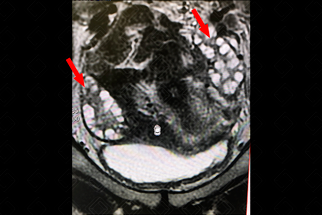

Texto alternativo para a imagem Créditos: Dra. Elazir Mota - Rio de Janeiro/RJ

Descrição da figura: Ressonância magnética da pelve no eixo coronal, imagem ponderada em T2 evidenciando ovários com volume aumentado bilateralmente (10 cc), com predomínio dos folículos na periferia dos ovários e mais de 12 folículos em cada ovário, permitindo que seja sugerido no laudo radiológico essa possibilidade diagnóstica (setas vermelhas).

Exames de imagem: A lguns achados de imagem podem permitir que o radiologista sugira essa possibilidade diagnóstica, preferencialmente, quando aliado a uma boa história clínica. Os achados de imagem que ajudam no diagnóstico de SOAP são: ovários com dimensões aumentadas (volume ovariano acima de 10 cc), folículos predominando na periferia ovariana e mais de 12 folículos por ovário medindo entre 2-9 mm. Os exames de imagem que devem ser solicitados de escolha para essa avaliação são ultrassonografia transvaginal (lembrando que nas pacientes virgens ou com algum outro fator que contraindique essa via, como vaginismo, podemos optar pela ultrassonografia pélvica por via suprapúbica) ou ressonância magnética da pelve (figura acima) .

Vale lembrar que a presença de apenas um ovário com as características descritas é suficiente para identificar o padrão.